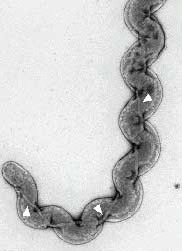

Лептоспиры: фотографии удивительных микроорганизмов